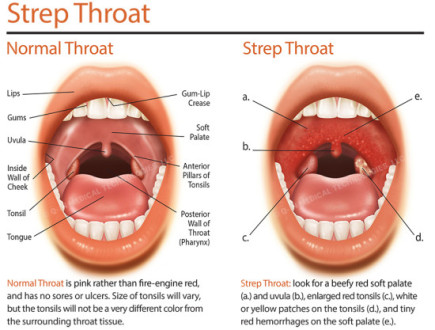

What Is Strep Throat And How Does It Differ From Common Sore Throat

fever, headache, VERY SORE THROAT W/ SUDDEN ONSET, TONSIL ERYTHEMA and …

acid reflux symptoms in throat, strep throat symptoms adults, all of sudden sore throat, sore throat no other symptoms, pharyngitis symptoms, ,